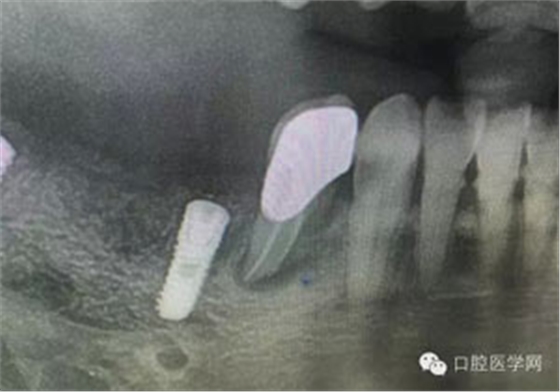

病例1:患者迫切希望保留自己的這一顆牙齒,根尖周陰影比較大,二度松動(dòng).而且旁邊有種植修復(fù)體,和患者溝通好后,治療好后觀察一個(gè)月后冠修復(fù),因?yàn)橛蟹N植的后期修復(fù),所以有了機(jī)會(huì)觀察,術(shù)后三個(gè)月和術(shù)后四個(gè)月,根尖恢復(fù)的還算不錯(cuò),希望能夠繼續(xù)觀察下去.這樣子的病例,做的時(shí)候我們一定要非常的小心,和患者要有充分的溝通以及不同科室的溝通然后決定怎么樣做比較好,假如就是出現(xiàn)了問(wèn)題,到時(shí)候我們也比較好處理些,免得我們自己到時(shí)候不好收?qǐng)觥?/span> 病例2:364647中齲的樹(shù)脂充填,現(xiàn)在樹(shù)脂的充填材料非常之多,有些時(shí)候,我們感覺(jué)有了好的材料我們就可以做出好的修復(fù),可是這是在我們有扎實(shí)的基本功的基礎(chǔ)上的,我們可以沒(méi)有那么好的樹(shù)脂,那么多的顏色選擇,修復(fù)的那么的逼真,但是我們至少要恢復(fù)患者牙齒的功能,將腐質(zhì)去除干凈,薄壁弱尖消除掉,選擇好適應(yīng)癥,給患者以盡可能好的修復(fù)。 來(lái)源于KQ88